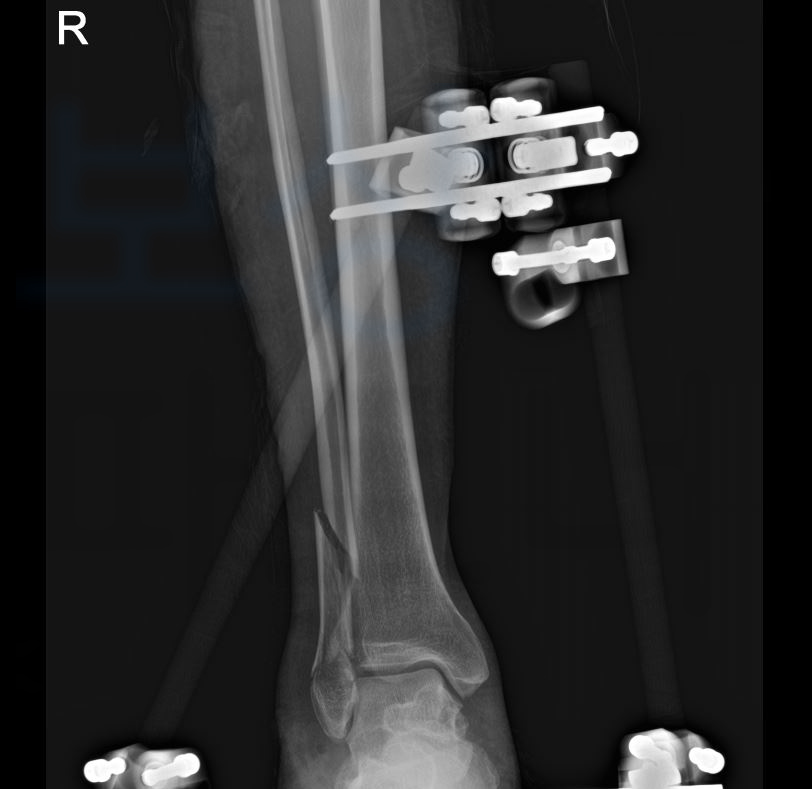

안녕하세요. 보상파트너입니다. 오늘은 비골 골절 뿐만 아니라 특히 거골 골절을 진단받아 수술한 경우 꼭 고려해야 할 산재 장해등급 기준! 소개해드리겠습니다. 먼저, 비골은 우리의 정강이 뼈의 비교적 얇고 가는 뼈를 비골이라고 합니다.

또한 거골은 발목을 이루는 뼈 중 하나로 경골, 비골의 바로 아래에 위치해 있고 발목 관절의 회전 운동을 담당합니다.

그런데, 특히 거골의 골절은 골절되기 쉽지 않은 부위인 만큼 심한 충격에 의해 발생하며 골절면의 정확한 정복이 되지 않을 경우 외상성 관절염이나 발목 운동의 제한과 같은 장해가 잔존할 수 있습니다.